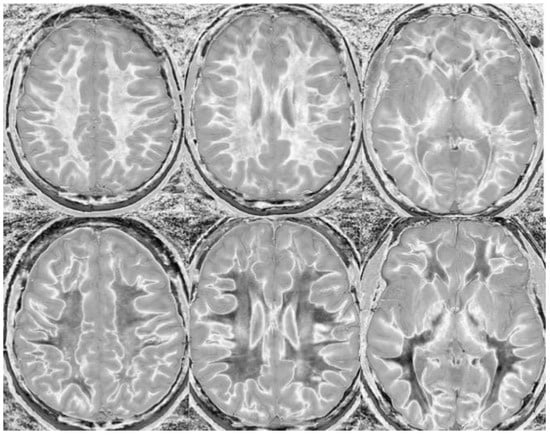

Figure 15.

Divided Subtracted Inversion Recovery (dSIR) in a patient with Grinker’s myelinopathy. Top row: Narrow middle domain dSIR images at the level of the centrum semiovale (left), corona radiata (middle), and basal ganglia (right) in a patient with persistent symptoms following prolonged hypoxia due to a suicide attempt. TIshort = 350 ms. TIlong = 500 ms. TE = 7 ms, TR = 5000 ms. There is a diffuse “white out”. Bottom row: T2-FLAIR images at matching levels show normal-appearing white matter. Scans were obtained 9 months following injury.

Figure 16.

Divided Subtracted Inversion Recovery (dSIR) in a patient with Grinker’s myelinopathy. Top row: Narrow middle domain dSIR images at the level of the centrum semiovale (left), corona radiata (middle), and basal ganglia (right) in a patient with persistent symptoms following prolonged hypoxia due to drug overdose. TIshort = 350 ms. TIlong = 500 ms. TE = 7 ms, TR = 5000 ms. There is widespread “white out”, with some sparing in the deep frontal lobe white matter. Bottom row: T2-FLAIR images at matching levels show normal-appearing white matter. Scans were obtained 2 years following injury.